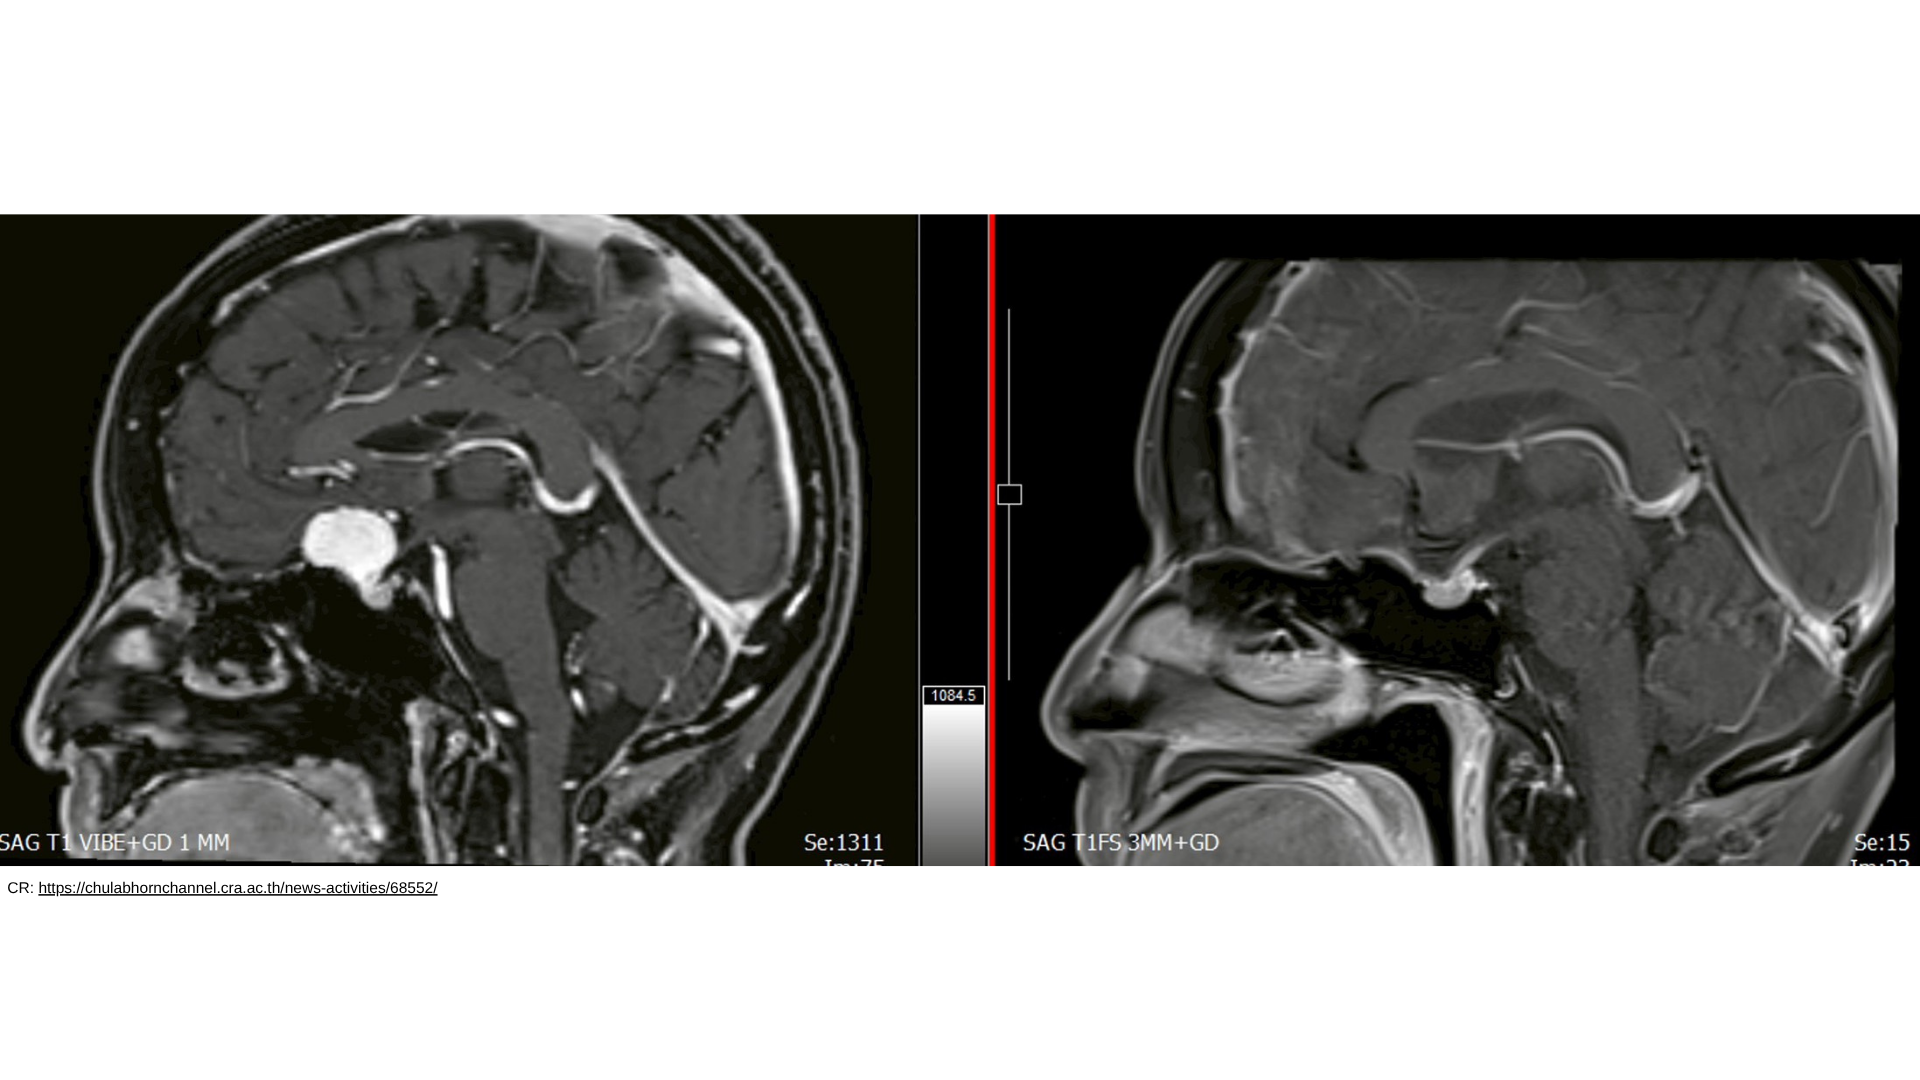

The procedure was led by Dr. Jonathan Aran Tangsrivimol, a neurosurgeon at the hospital, who treated a patient with a tumor located at the anterior skull base using the advanced Eyebrow Keyhole Approach. This highly precise surgical technique allows access to the brain through a small incision hidden within the eyebrow, significantly reducing trauma to surrounding brain tissue and critical structures.

The surgery utilized a combination of advanced technologies, including surgical microscopes, endoscopic visualization, and navigation systems, enabling high accuracy throughout the procedure. Compared to traditional open skull surgery, this minimally invasive method offers multiple benefits, including reduced surgical impact, shorter hospital stays, and faster recovery times.